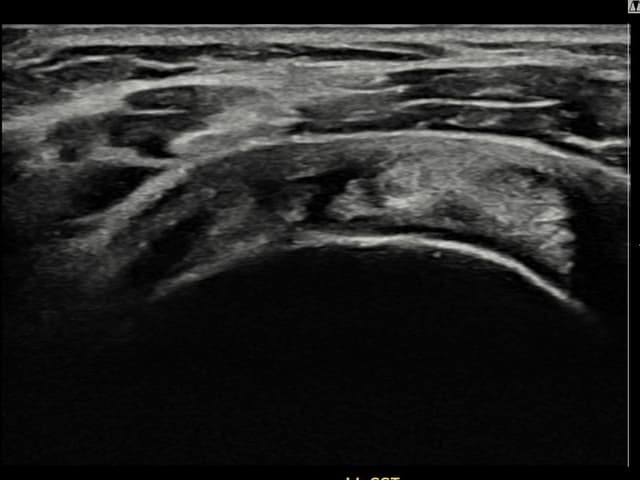

[経過期間: 23.07.18~23.09.14]

[縫縮術] 超音波検査にて左 棘上筋腱 광범위 部分断裂(15mm × 6mm (腱厚の約70%欠損))を確認。縫縮術施行後、腱の連続性が回復し、日常生活に復帰されました。